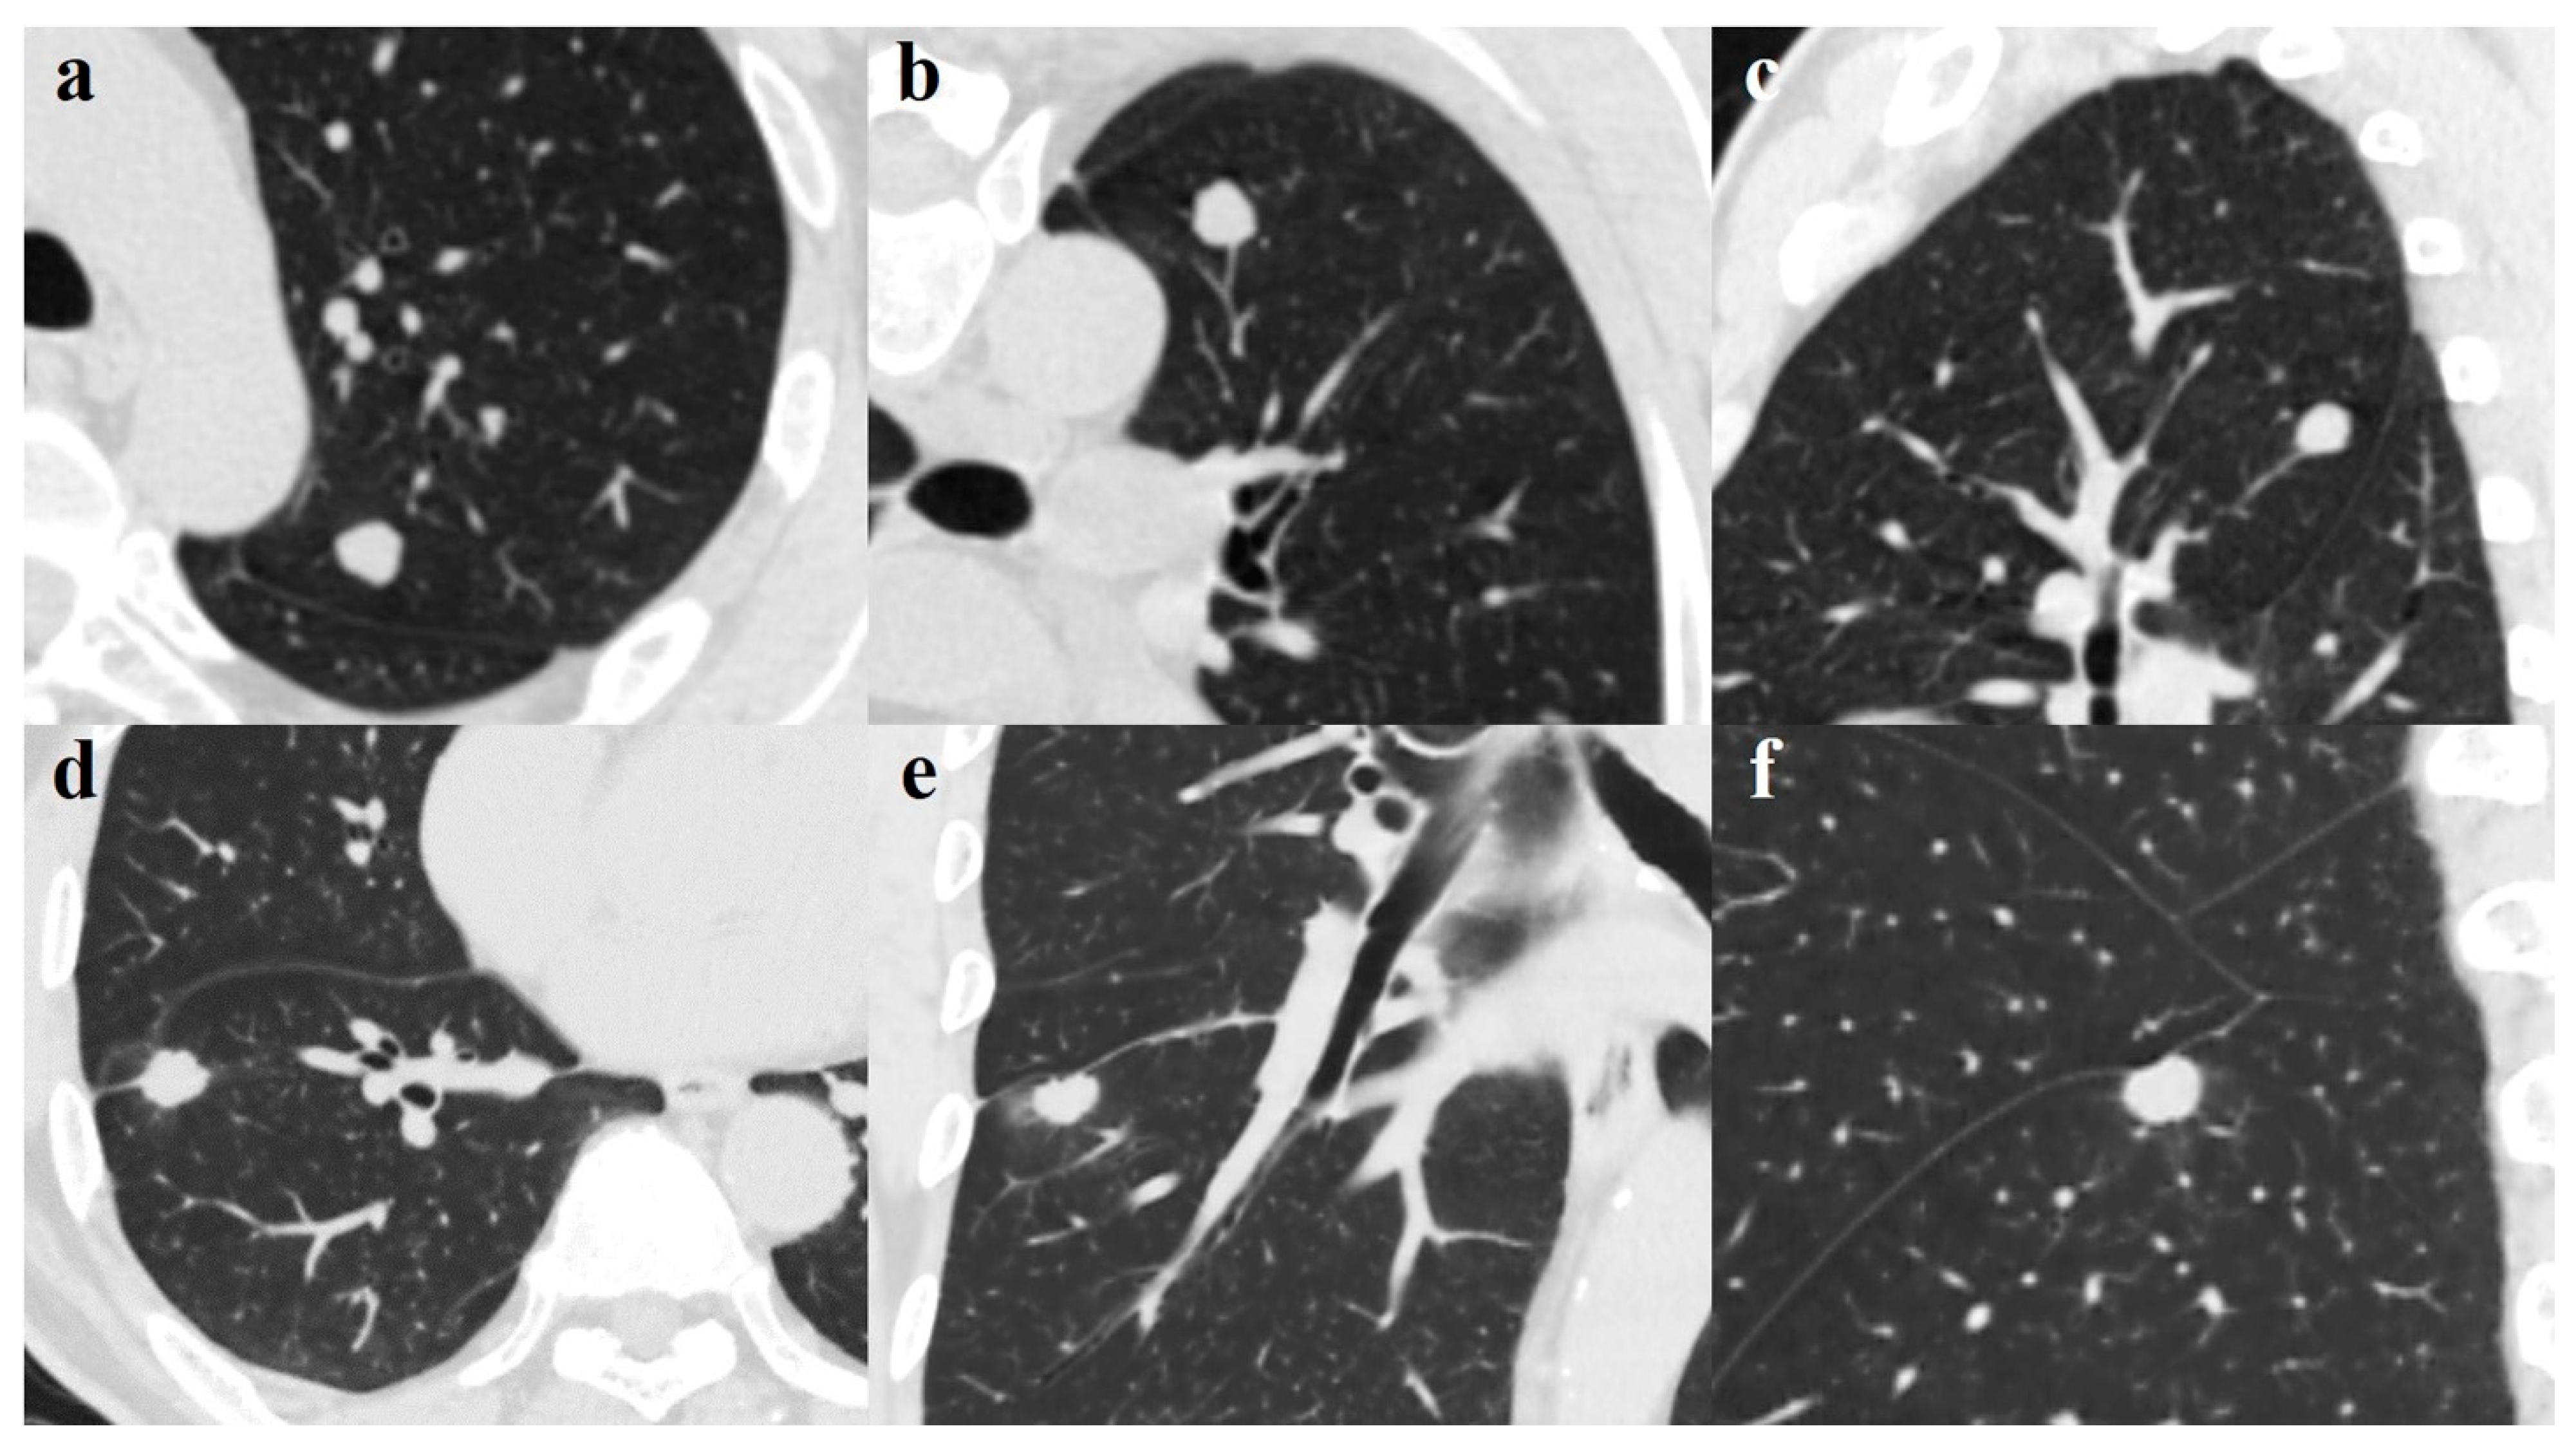

Stepwise multivariate logistic regression analysis with tuberculoma as an outcome was performed to derive the optimal variables that could discriminate tuberculoma from adenocarcinoma and to build the model. Variables with significant differences in the univariate analysis were all included. Ultimately, age, lobulation, and pleural indentation remained significant and were selected for model building, and an ROC curve with a statistically significant area under the curve (AUC) was obtained (0.956; 95% CI 0.901–1.000) (Figure 2). The sensitivity, specificity, and accuracy in discriminating tuberculoma and adenocarcinoma were 87.1%, 93.3%, and 90.2%, respectively; the positive predictive value (PPV) was 93.1% (95% CI 79.8–93.9), and the negative predictive value (NPV) was 87.5% (95% CI 85.7–88.2). These analyses indicate that age in combination with lobulation and pleural indentation showed an excellent capacity in discriminating noncalcified, solitary pulmonary tuberculoma and solid adenocarcinoma with a maximum diameter of 2 cm or less. The Hosmer–Lemeshow test (p-value > 0.05) and assessment of bootstrap calibration curves suggested an adequate model fit. Figure 3 provides representative chest computed tomography images of noncalcified pulmonary tuberculoma and solid adenocarcinoma.

Figure 3. (ac). A 49-year-old man with pulmonary tuberculoma in the upper lobe of the left lung. Axial image (a) showing a round-like well-defined solid nodule measuring 1.14 cm; blood vessel convergency can be seen on the reconstructed coronal (b) and sagittal (c) views. The lesion was confirmed on pathological diagnosis as a tuberculoma. d-f. A 65-year-old man with lung adenocarcinoma in the right lower lobe. Axial image (d) demonstrates a well-defined juxta-fissural solid nodule measuring 1.47 cm with lobulated margin, short burr, and pleural indentation sign. Perilesional ground-glass opacification and a pleural indentation sign can be seen on the coronal (e) and sagittal (f) views. The lesion was proven on pathological diagnosis to be a moderately differentiated adenocarcinoma.